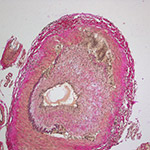

Choroidal Neovascular Membrane

A problem that is related to a wide variety of retinal diseases,